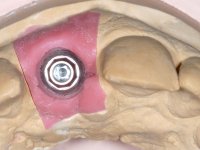

After performing an impression of the implant and making the models, we tested several rehabilitative options with the help of the implant brand planning kit. None proved capable. In this sense and as a resource solution, an innovative solution was proposed. It was proposed to make a milled Zr abutment with an appropriate design to receive a veneer that would hide the screw access hole. The veneer itself had a ceramic-coated Zr infrastructure. The goal was to achieve retention and strength by screwing the abutment and aesthetically solve the case with the veneer.

After the impression of the implant using a double-mix technique with double viscosity and the collection of shape and color information by the ceramist, we proceed with the work. In the model, a syn octa was placed over the implant, and a screw was placed on it to assess its emergence in relation to the incisal edge. Then, an adequate emergence profile in the artificial gingiva was prepared. A abutment with characteristics suitable for overbite and simultaneously capable of receiving a veneer was waxed on top of this scenario. This waxing gave rise to the manual milling of a very personalized abutment. An infrastructure in Zr was also made for the veneer with a very great adaptation to the abutment. On this infrastructure ceramics were placed. Ceramic fluorescence sought to compensate for the lack of fluorescence that Zr had and obviously further customize the aesthetics. The adhesive bridge was removed and the definitive work was placed. The syn octa was initially tightened with 35 N to the implant and then the Zr abutment was tightened over the syn octa with 15 N. The access hole was plugged and then the veneer was cemented with resin-reinforced glass ionomer. After 15 years, the patient returned to the consultation with tooth mobility. Fortunately, nowadays we have the possibility of having dynamic tightening wrenches that allow tightening screws with greater inclinations. An access cavity was made without damaging the incisal edge of the veneer. Tightening was done with a dynamic wrench with 15 N torque. The hole was covered with Teflon and filled with composite resin. This solution allowed the problem to be solved in a simple and economical way.